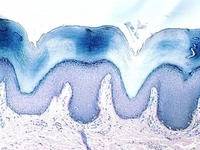

Transitional epithelium

- Epidermis

- Thick skin